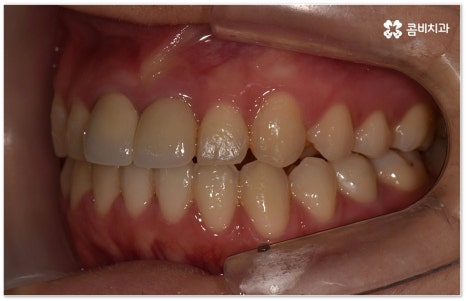

요즘 가장 많이 쓰이는 치아교정장치 인 클리피씨는 치아 색상의 세라믹 브라켓을 이용하기 때문에 심미성도 뛰어나고 자가결찰방식을 이용하여 보다 적은 힘으로 지속적이고 부드러운 치아 이동을 할 수 있도록 고안된 장치이므로 통증을 줄여줄 뿐 아니라 보통 2년 남짓 걸렸던 전체 교정 기간 역시 6개월 정도 감소시켜 줄 수 있습니다. 환자분들의 상황에 따라 내원 횟수 역시 줄일 수 있기 때문에 업무가 많이 바쁜 직장인분들의 경우에도 이용할 수 있다는 장점을 가지고 있어요.

이때 환자분들의 상황에 따라서 구조적인 원인이 크지 않고 교합이 심하게 어긋나지 않은 상태에서 치아의 각도만 살짝 앞으로 튀어나와 있거나 사이가 조금 벌어져 있는 등 부분 교정으로 치열을 가지런하게 바로잡을 수 있는 케이스도 있는데 이런 경우 6~8개월 정도의 보다 짧은 기간에 간편하게 치료를 끝낼 수 있으니 먼저 꼼꼼한 검진을 통해 자신이 부분 교정이 가능한지 여부를 알아보시면 좋을 거예요.

부정교합을 개선할 때 교합이 어긋난 정도가 심하고 구조적인 원인이 커서 부분 교정이 아닌 전체 교정이 필요한 케이스인 경우라고 해도 말씀드렸던 클리피씨 교정 장치 또는 보다 심미성을 강조한 치아교정장치 들의 도움을 통해 다른 사람과 얘기를 하거나 음식을 먹을 때 브라켓이 두드러지게 드러나는 부담을 줄일 수 있으니 설측교정, 콤비교정, 투명교정, 인비절라인 등에 대해서 한 번 알아보시고 각자에게 맞는 방법으로 교정 치료를 시작해 보시길 권유드리고 있어요.